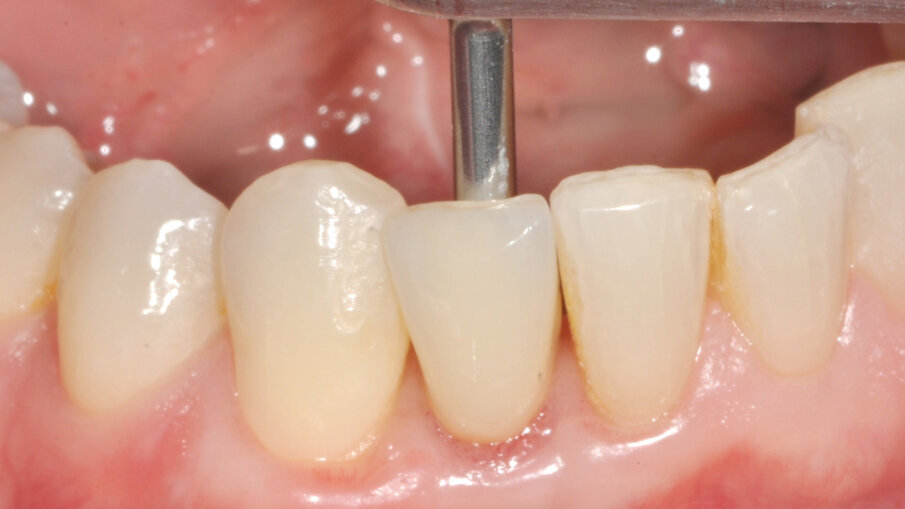

Zavedení implantátu

Pacient byl objednán na kontrolu týden po chirurgickém zákroku. V té době bylo dosednutí provizorní náhrady shledáno uspokojivým (obr. 11). Obrázek 12 zachycuje digitální plánování abutmentu Atlantis Crown Abutment ze zirkonu s adekvátním prostorem pro vrstvy keramiky. Definitivní náhrada byla vyrobena v zubní laboratoři s ohledem na dosažení harmonie se sousedními zuby (obr. 13). Byl také vytvořen prostor pro aproximální papilu. Abutment kotvený šroubkem s lingválním přístupem lze vidět na obrázku 14. Provizorní náhrada byla vyměněna za definitivní (obr. 15). Subgingivální část abutmentu poskytla oporu měkkým tkáním a byl zajištěn prostor pro mezizubní papilu. Atlantis Crown Abutment byl dotažen točivým momentem 25 Ncm (obr. 16). Lingvální přístup ke šroubku byl nejprve zakryt výplňovým materiálem (PTFE) a poté kompozitem. Následně byl pořízen další RTG snímek implantátu s upevněným definitivním abutmentem Atlantis Crown Abutment (obr. 17). Na obrázku 18 lze vidět konečný výsledek s definitivní náhradou, na němž je patrný adekvátní obrys měkkých tkání a vyplnění aproximálního prostoru. Keramika rovněž dokonale napodobila odstín sousedních zubů.